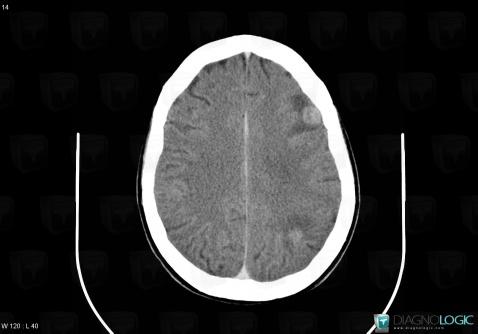

Toxoplasmosis, Basal ganglia and capsule, CT

Here is the specific information in the key image above:

- Diagnosis Toxoplasmosis (link to Abscess), Location(s) Basal ganglia and capsule, with gamuts Basal ganglia hypodense lesion